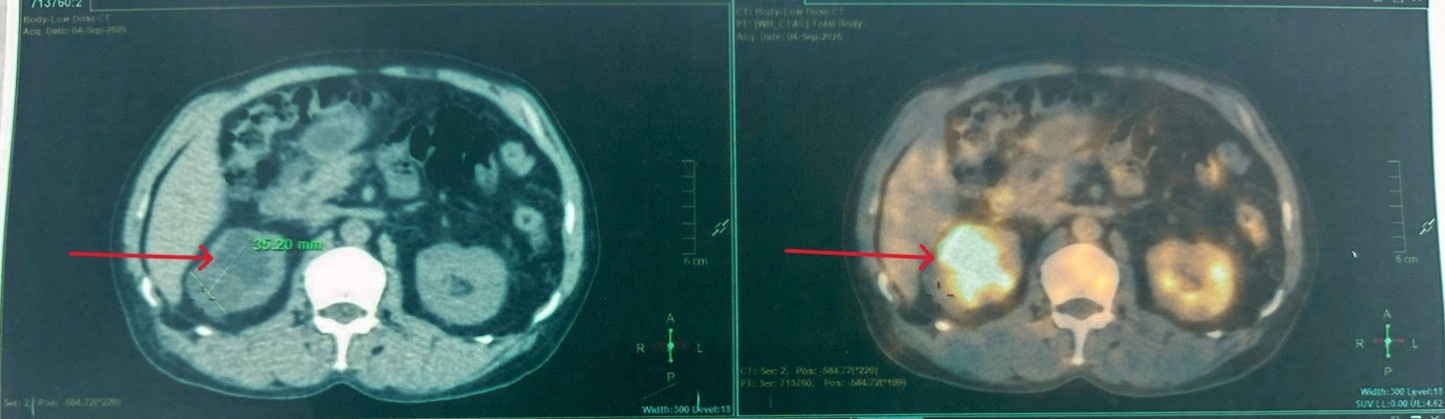

– Chụp CT bụng: Hình ảnh giãn đài bể thận và niệu quản phải do sỏi niệu quản đoạn 1/3 trên. Sỏi đài dưới thận phải.

Hình 2: Thận phải: Hình dạng và kích thước bình thường, nhu mô có nang 32mm. Đài bể thận giãn đường kính trước sau 15mm, đài dưới có sỏi kích thước 5mm. Niệu quản đoạn 1/3 trên giãn đường kính 9mm, có sỏi kích thước 7x13mm.

Hình 5: Hình ảnh đài – bể thận phải giãn độ II, còn sonde JJ niệu quản – bàng quang, nang thận phải đường kính 35 mm